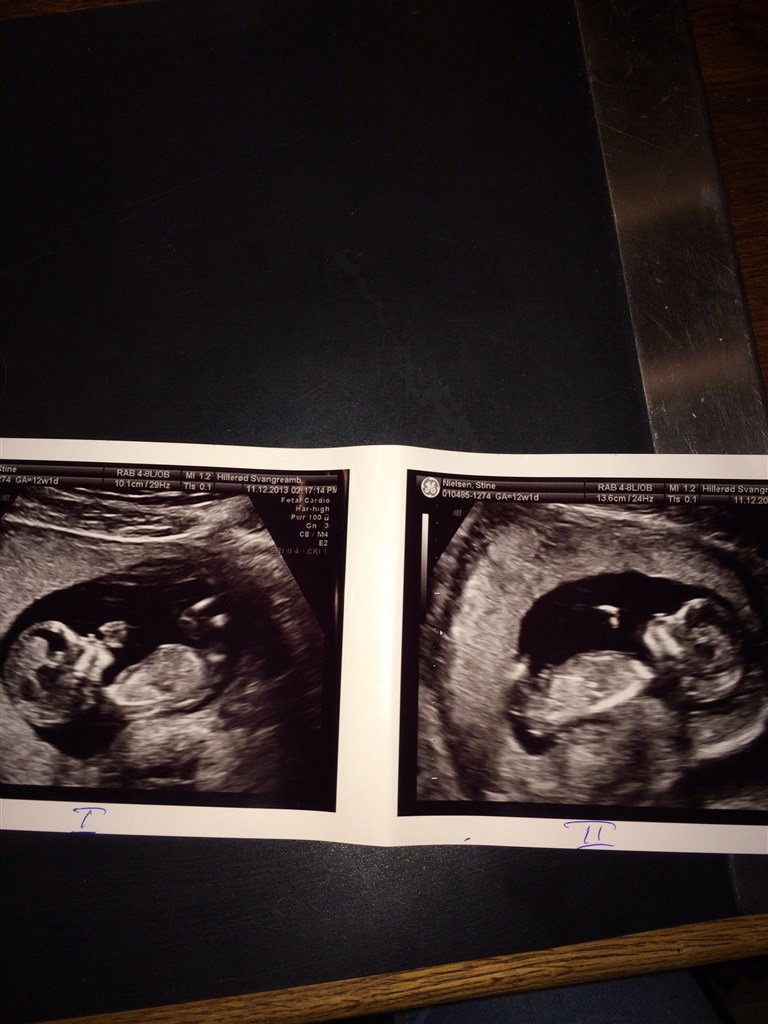

Sådan så det ud til nf

Vedhæftede fotos (klik for at se i fuld størrelse)